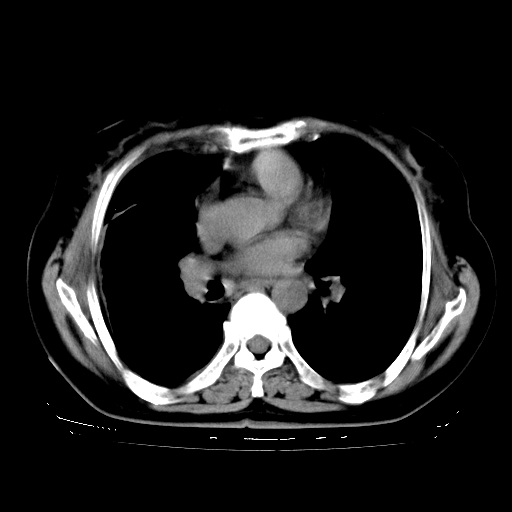

以下是引用zhangzhongshou在2008-3-22 12:52:00的发言:[br]1、右侧液气胸。[br]2、腹水。建议进一步检查。

以下是引用鲁巨ct在2008-3-22 14:10:00的发言:[br]1、右侧液气胸,右中下叶节段性不张。[br]2、腹水,建议上腹部ct检查

以下是引用zjzjr在2008-3-22 17:19:00的发言:[br]1、右侧液气胸,右下叶节段性不张。[br]2、腹水,建议上腹部ct检查